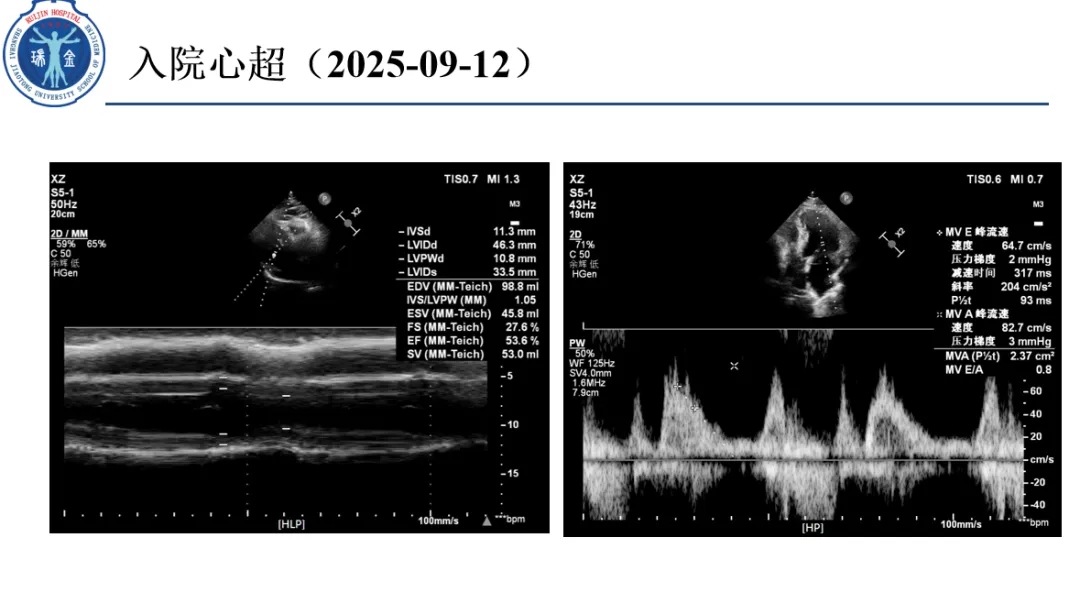

病例名称:胸痛晕厥“谜案”:冠脉造影大致正常为何险象环生?